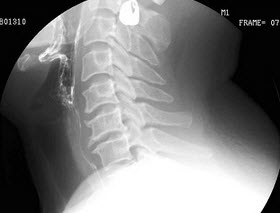

123、单项选择题

女,45岁,咽喉不适,异物感。体检:仅见慢性咽炎改变,结合图像,最可能的诊断为()

A.正常表现

B.会厌征

C.颈椎退变

D.食管型颈椎病

E.以上都不是